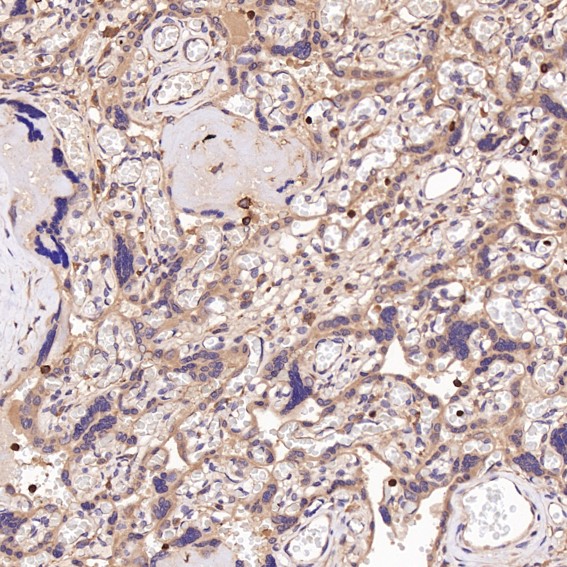

CD45 Antibody (CY5311)

Application:WB,IHC,ICC/IF,FC

Reactivity:Human

Source:Rabbit mAb